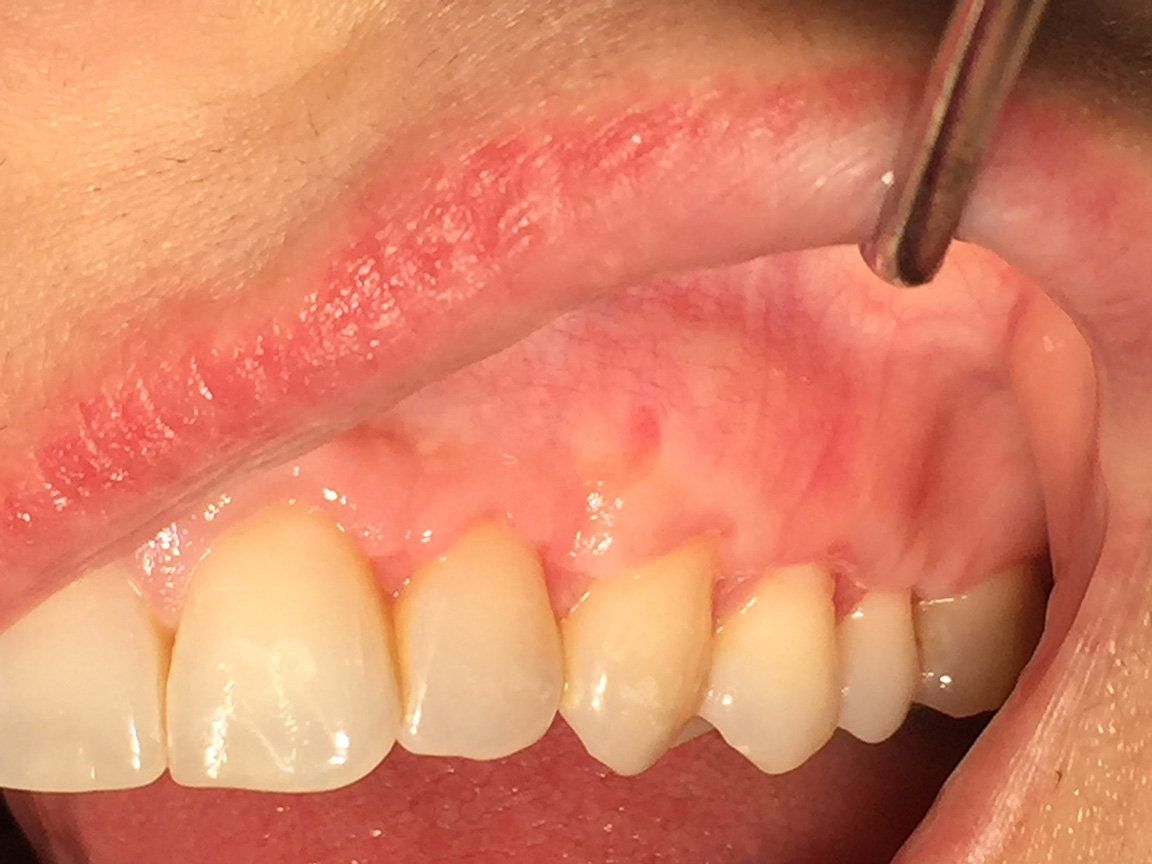

Correzione SIMULTANEA di recessioni multiple su quadrante sup sx con tecnica bilaminare di chirurgia mucogengivale, con innesto di connettivo autologo.

Photogallery: